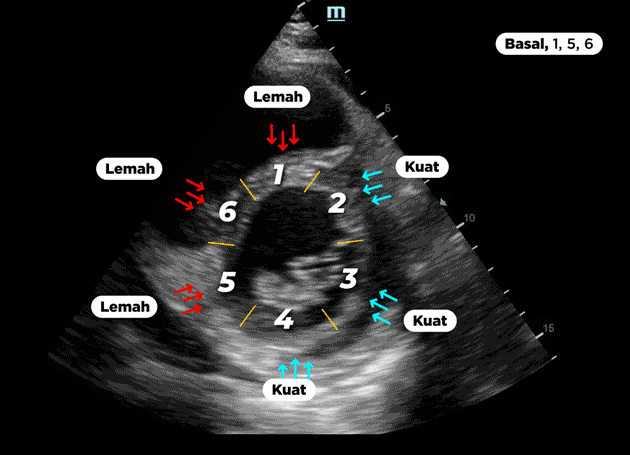

BERIKUT ADALAH HASIL ECHO JANTUNG PASIEN YANG TELAH MENGALAMI KELEMAHAN OTOT JANTUNG

Basal : Hipokinetik Anterior, Anteroseptal dan Inferoseptal

Gambar berikut adalah hasil pemeriksaan gerakan otot jantung pada ke 6 segment bagian Basal jantung. Tanda panah berwarna merah pada segment 1,6 dan 5 menunjukkan adanya kelemahan (Hipokinetik) pada gerakan otot jantung. Hipokinetik merupakan kondisi dimana bagian otot jantung tidak mampu melakukan kontraksi dengan baik, hal ini disebabkan oleh penyumbatan pada pembuluh darah jantung. Coba bandingkan dengan gerakan otot jantung normal pada segment 2,3 dan 4 (Panah biru).

Ketika terjadi penyumbatan pada arteri koroner, regio jantung tertentu akan mengalami kekurangan aliran darah dan menyebabkan gerakan yang abnormal tergantung pada segment mana yang terkena dan pembuluh darah mana yang mengalami penyumbatan. Dari hasil ECHO diatas menunjukkan dari 6 segment jantung, terdapat 3 segment yang mengalami kelemahan.

Lalu bagaimanakah gerakan otot jantungnya?? Perhatikan hasil echo berikut ini

Tanda panah pada bagian 1, 5 dan 6 menunjukkan bahwa gerakan jantung tersebut mengalami kelemahan sehingga tidak mampu melakukan kontraksi jantung.

Hal ini terjadi akibat tersumbatnya pembuluh arteri yang membawa nutrisi ke otot jantung. Dari 6 segment jantung terdapat 3 segment yang mengalami kelemahan.